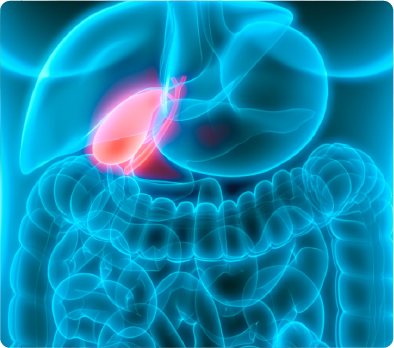

什麽原因導(dao)緻自己長(zhang)了(le)膽囊息肉?

成(cheng)因非(fei)常複雜,可(kě)能(néng)與下列相關因素有(yǒu)關